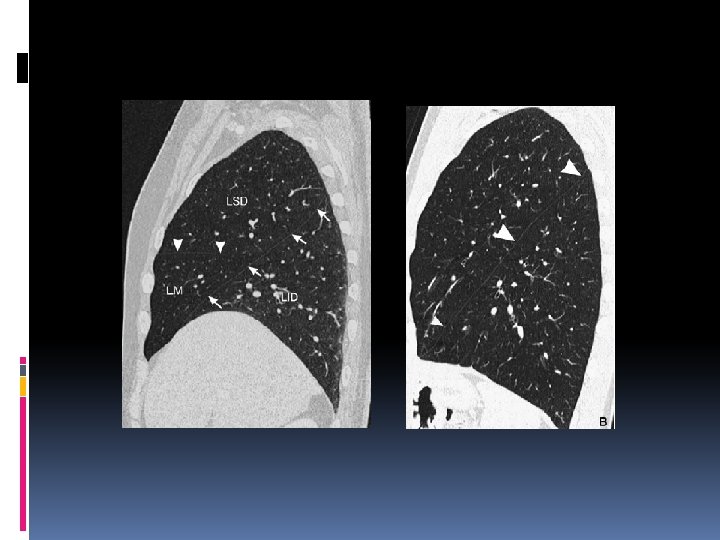

TDM: Sur les coupes axiales o en dedans le médiastin o en dehors la petite scissure verticalisée o en arrière la grande scissure (orientation frontale ). Les signes indirets sont plus nets

A la TDM : forme triangulaire à sommet postérieur en dehors et en arrière par la grande scissure et le lobe inférieur venant faire une hernie postérointerne : signe de Luftsichel.

Sur le profil : L’opacité se projette sur le rachis Effacement de la coupole homolatérale Sur la TDM : le lobe occupe la gouttière latérovertébrale limite antéroexterne : la grande scissure.